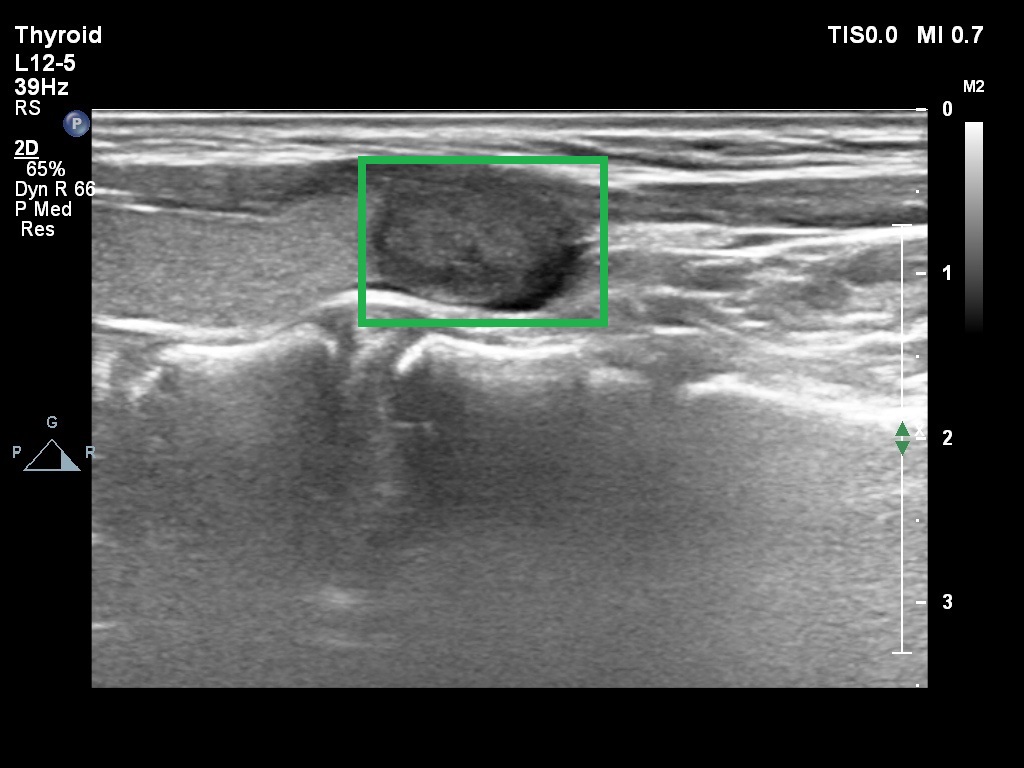

[With nodule]

We use the thyroid ultrasound dataset from pham2021evaluating that contains 14171 thyroid ultrasound images of 970 Vietnamese patients. Samples are shown in Fig. 1, and medical experts label the nodule locations.